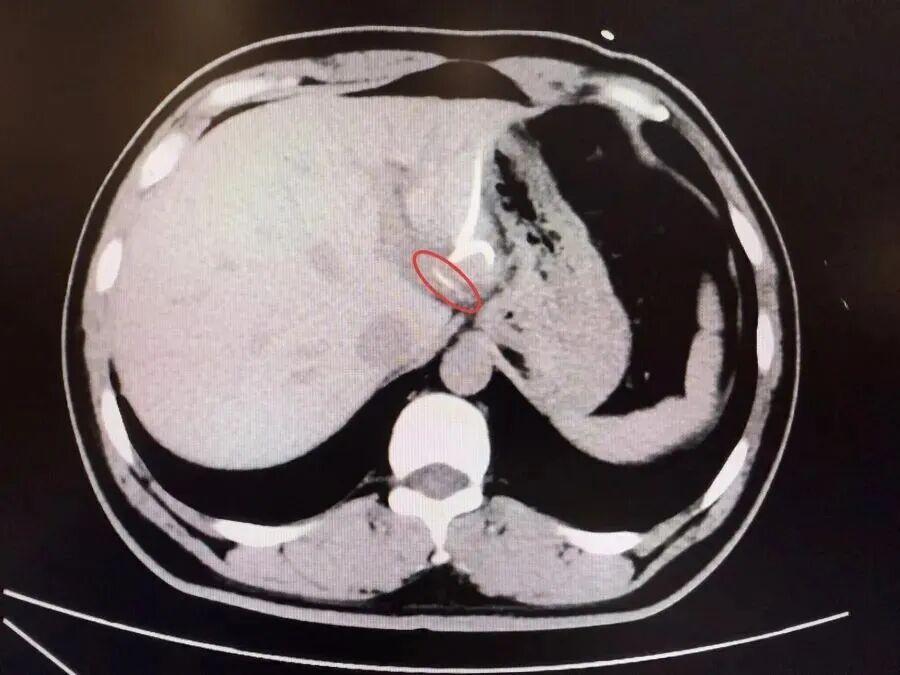

半月前,37岁的李先生(化名)误吞鱼刺却未察觉,数天后出现腹痛、高热(达40℃)等症状,当地医院诊断为“肝脓肿”,治疗后症状反复,ct检查才发现肝脏左叶有鱼刺——其已穿透胃壁入肝引发感染,十分危险,当地医生评估后认为,要彻底清除异物,需要进行左半肝切除手术,这让李先生难以接受。

为寻求更精准、微创的治疗,李先生转至复旦大学附属中山医院内镜中心。“鱼刺位置非常凶险,就在贲门旁刺入左肝,紧贴大血管。”接诊的周平红主任指出,腹腔感染粘连严重,手术难度极高。